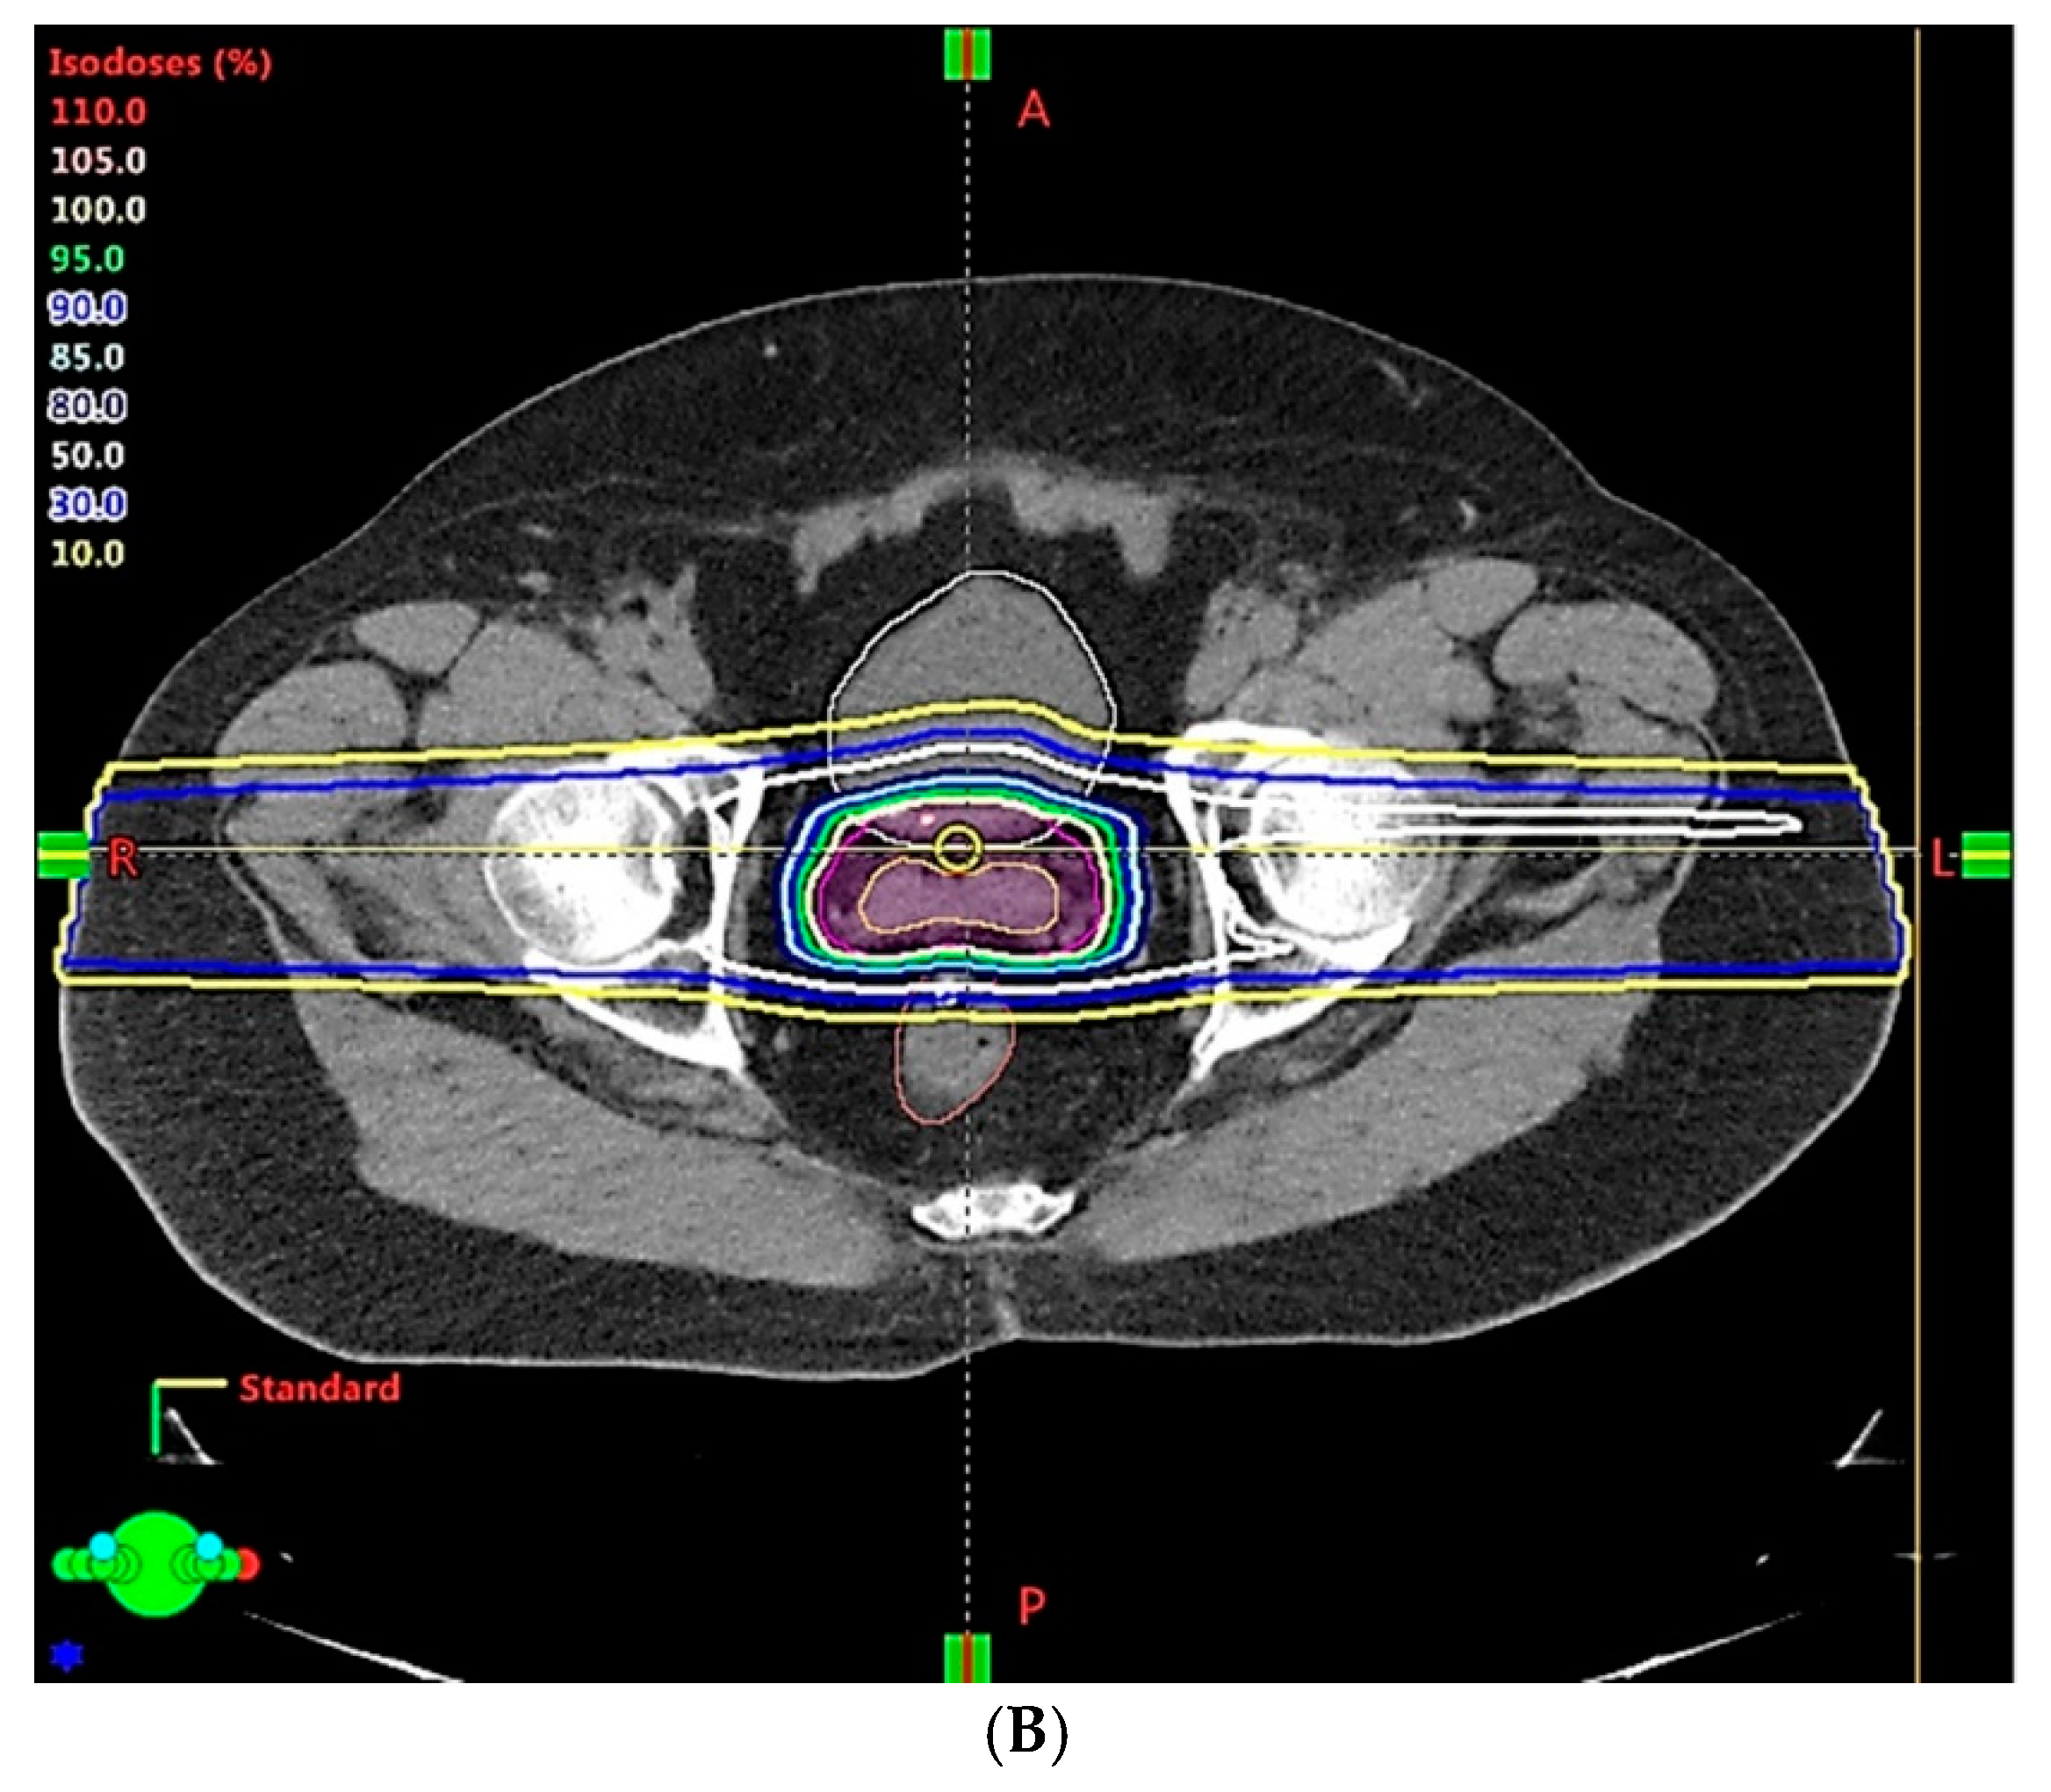

- Because of the inferior soft tissue contrast, orthogonal X-ray imaging systems rely on bony structures for verification of treatment position during patient setup. This type of setup technique can result in large positioning errors due to daily movement of the target and organs at risk (OARs) relative to the bony structures in the former technique. With fiducial markers implanted inside the prostate, many studies concluded that image registration by fiducial markers would reduce matching error. However, some patients may not accept marker implantation. Migration of markers with time may introduce registration errors. Such problems can now be minimized using on-board cone beam CT (CBCT). The better image quality of CBCT can provide 3D images and more information on the anatomic relationships between organs [64,65], which can be used to improve the accuracy of patient setup. Besides patient positioning, CBCT images can also provide information about inter-fractional changes in patient anatomy. In a recent study, an image-based correction method to generate pseudo-CT images from CBCT images was investigated for possible application in proton dose calculations [66] in adaptive PT. MRI, which has the ability to offer fast real-time imaging with high soft tissue contrast in the absence of ionizing radiation exposure [67], is being investigated for use in patient setup in RT. Our study using an external MRI setup room [68] and studies by others [69] indicated that patient positioning accuracy on the order of 1 mm is feasible, and is a significant reduction from that of conventional setup systems.